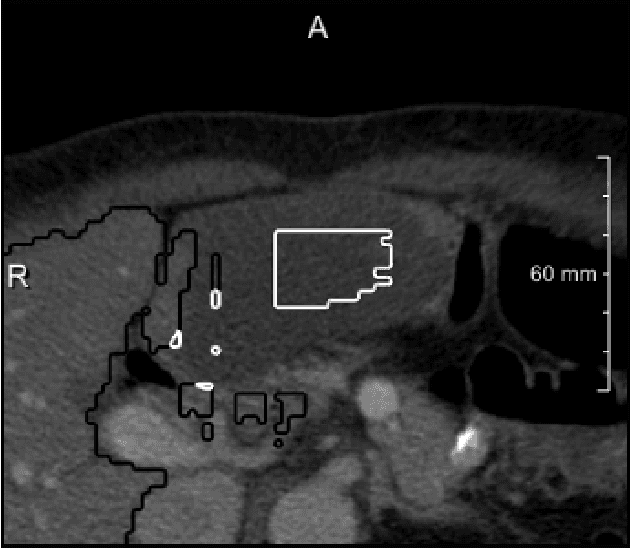

We present a fully automatic method employing convolutional neural networks based on the 2D U-net architecture and random forest classifier to solve the automatic liver lesion segmentation problem of the ISBI 2017 Liver Tumor Segmentation Challenge (LiTS). In order to constrain the ROI in which the tumors could be located, a liver segmentation is performed first. For the organ segmentation, an ensemble of convolutional networks is trained to segment a liver using a set of 179 liver CT datasets from liver surgery planning. Inside of the liver ROI a neural network, trained using 127 challenge training datasets, identifies tumor candidates, which are subsequently filtered with a random forest classifier yielding the final tumor segmentation. The evaluation on the 70 challenge test cases resulted in a mean Dice coefficient of 0.65, ranking our method in the second place.